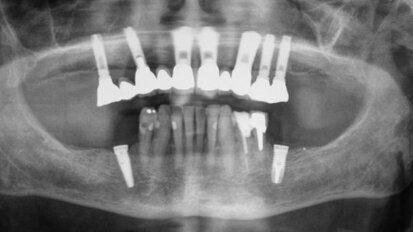

Titanium implants may carry risk of corrosion